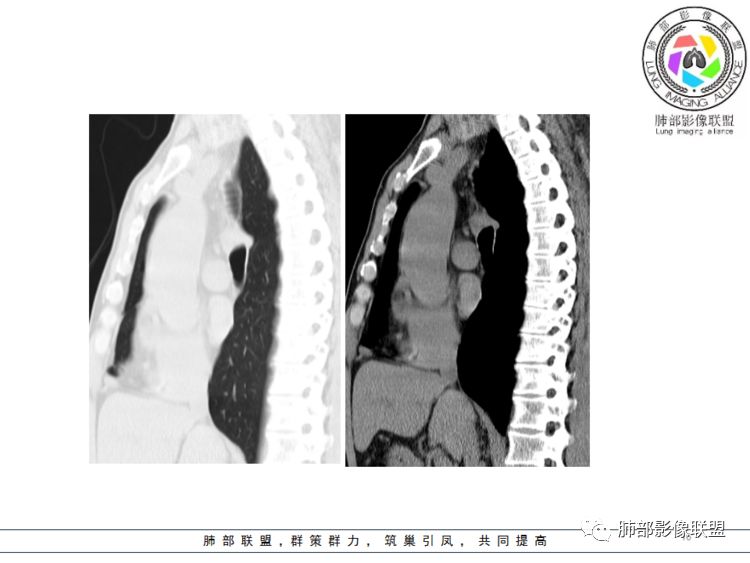

南边分析:针对本例,病灶跨气管壁内外生长,常规跨内外的有:恶性肿瘤为主,其次就是神经源性、平滑肌瘤;常规的思维:跨内外就要看结构的变化气管的优势在于软骨相对密度高,而且成C型

我们如何分析这个病例?冠状位:软骨密度稍高;病灶区软骨部分区域不连续,外围连续,提示病灶推移为主,不是破坏为主;如果破坏,应该这些软骨显示不清,移位不明显

病灶从软骨见推移开,跨内外,因此定在良性。恶性是侵犯,破坏为主,如果破坏,应该这些软骨显示不清,移位不明显,不是推移为主这例病变定在良性,我们就要考虑:1、软骨之间的平滑肌来源;2、神经源性

南边:需要用连续的窄窗观察。